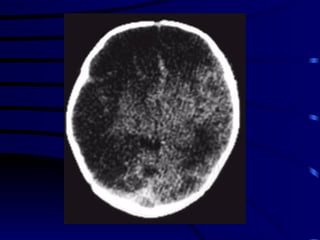

DIAGNOSTICO AIT : clínica, TAC o RMN positiva en el 15 al 30 % de los casos. Ictus establecido:  TAC no es útil en las primeras 24 hs. de una isquemia. RMN: detecta infartos a partir de las primeras 3 hs. TAC : pone en manifiesto el 100% de los hematomas.

DIAGNOSTICO AIT :clínica, TAC o RMN positiva en el 15 al 30 % de los casos. Ictus establecido: TAC no es útil en las primeras 24 hs. de una isquemia. RMN: detecta infartos a partir de las primeras 3 hs. TAC : pone en manifiesto el 100% de los hematomas.